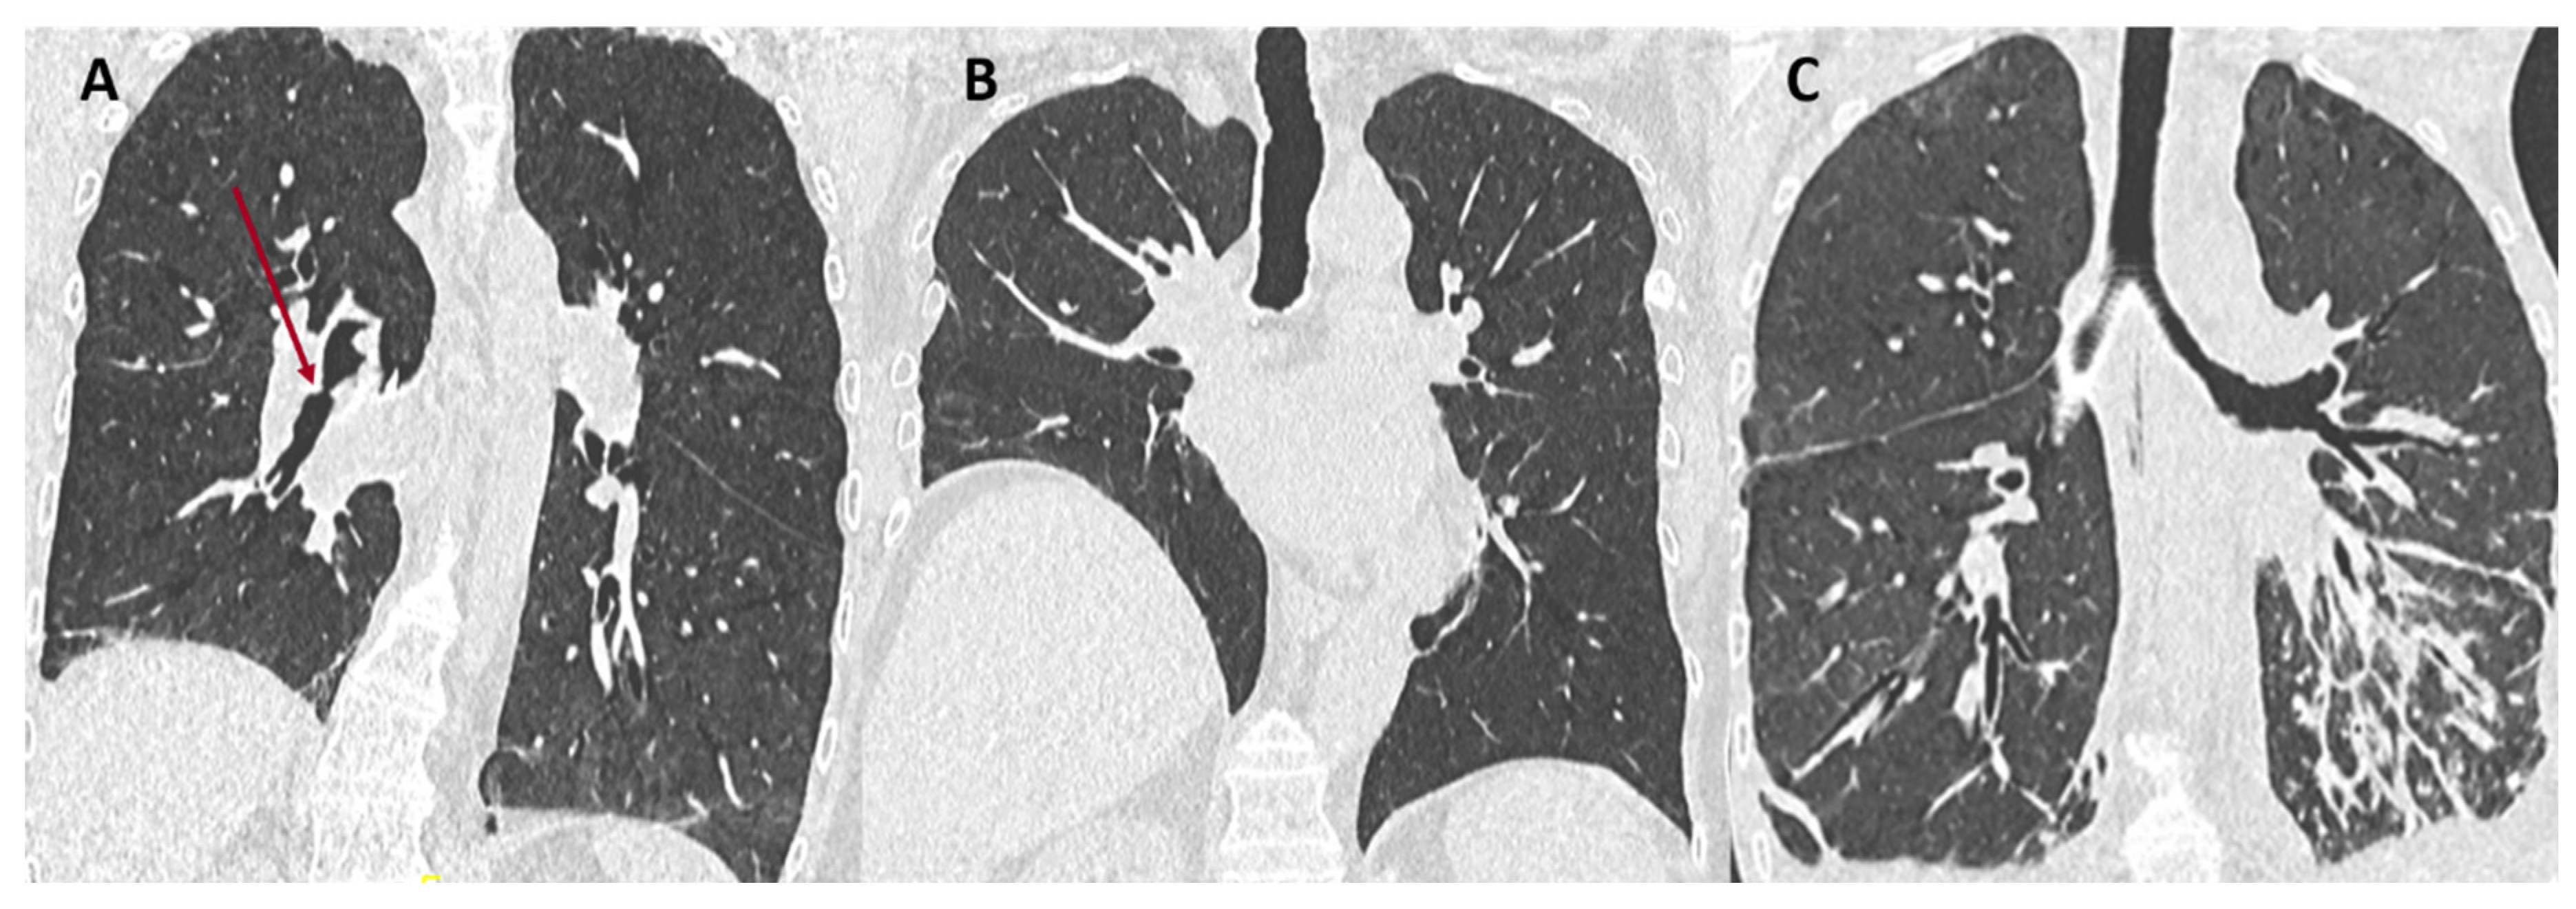

- Byrne, D.; Nador, R.G.; English, J.C.; Yee, J.; Levy, R.; Bergeron, C.; Swiston, J.R.; Mets, O.M.; Muller, N.L.; Bilawich, A.-M. Chronic Lung Allograft Dysfunction: Review of CT and Pathologic Findings. Radiol. Cardiothorac. Imaging 2021, 3, e200314. [Google Scholar] [CrossRef] [PubMed]

- Verleden, S.E.; de Jong, P.A.; Ruttens, D.; Vandermeulen, E.; Van Raemdonck, D.E.; Verschakelen, J.; Vanaudenaerde, B.M.; Verleden, G.M.; Vos, R. Functional and computed tomographic evolution and survival of restrictive allograft syndrome after lung transplantation. J. Heart Lung Transplant. 2014, 33, 270–277. [Google Scholar] [CrossRef] [PubMed]

- Glanville, A.R.; Verleden, G.M.; Todd, J.L.; Benden, C.; Calabrese, F.; Gottlieb, J.; Hachem, R.R.; Levine, D.; Meloni, F.; Palmer, S.M.; et al. Chronic lung allograft lung dysfunction: Definition and update of restrictive allograft syndrome. A consensus report from the Pulmonary Council of the ISHLT. J. Heart Lung Transplant. 2019, 38, 483–492. [Google Scholar] [CrossRef]

- Konen, E.; Weisbrod, G.L.; Pakhale, S.; Chung, T.; Paul, N.S.; Hutcheon, M.A. Fibrosis of the Upper Lobes: A Newly Identified Late-Onset Complication After Lung Transplantation? Am. J. Roentgenol. 2003, 181, 1539–1543. [Google Scholar] [CrossRef]

- Verleden, S.E.; Ruttens, D.; Vandermeulen, E.; Bellon, H.; Dubbeldam, A.; De Wever, W.; Dupont, L.J.; Van Raemdonck, D.E.; Vanaudenaerde, B.M.; Verleden, G.M.; et al. Predictors of survival in restrictive chronic lung allograft dysfunction after lung transplanttion. J. Heart Lung Transplant. 2016, 35, 1078–1084. [Google Scholar] [CrossRef]